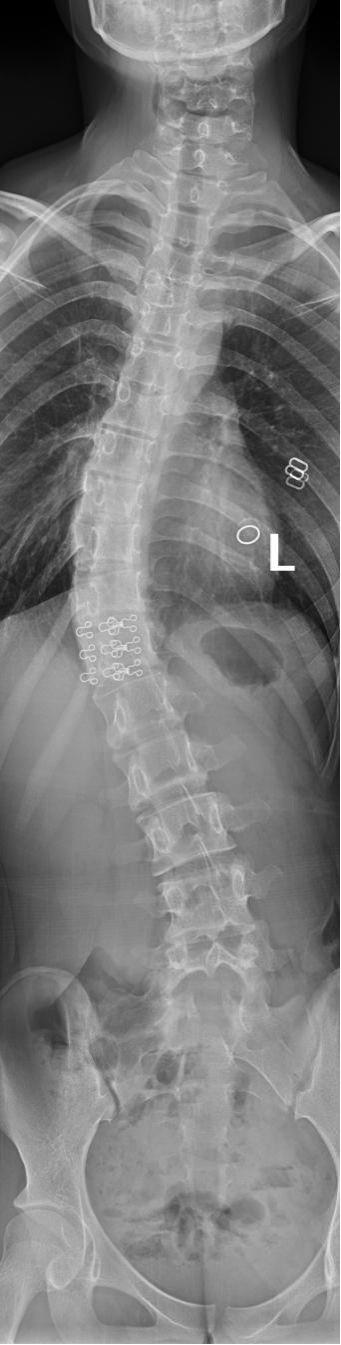

脊柱全长DR摄影技术是一种先进的检查方式,解决了全脊柱不能一次成像的问题,经过4-5次的曝光后,可以完成脊柱全长的站立负重位摄影,通过拼接技术,将多张X线片进行拼接,形成一个完整的脊柱全长影像,这种技术可以更直观、更全面、更准确的观察脊柱的整体形态,帮助评估侧弯的程度,极大的方便了病情的分析,为临床的诊断和治疗提供了重要的影像学依据。对侧弯的治疗方式和治疗后的评估提供了极为重要的参考价值。

脊柱全长DR摄影

脊柱全长DR摄影技术的应用:

1、脊柱侧弯:显示侧弯的角度和弯曲的部位,根据弯曲的程度制定治疗方案。

5、脊柱侧弯矫正效果的评估,定期的复查,医生可以观察侧弯程度的变化,评估矫正的效果,从而调整治疗方案。